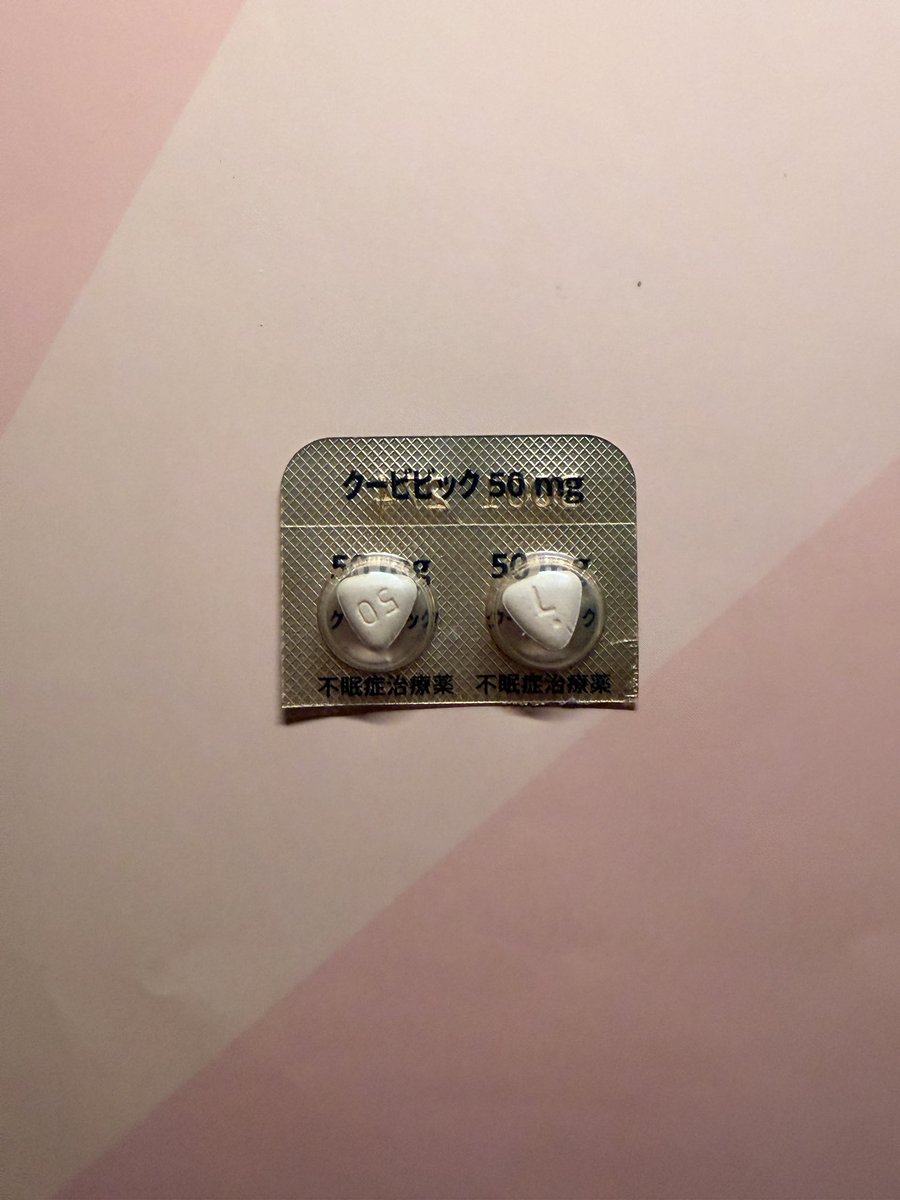

一些白兔27t的体验:

没有服用会干扰酶的药物或食物。

睡眠期间心率和血氧的数据比平时低一些。总之没有发生什么很特别的事。 https://t.co/PAXqkakGGo